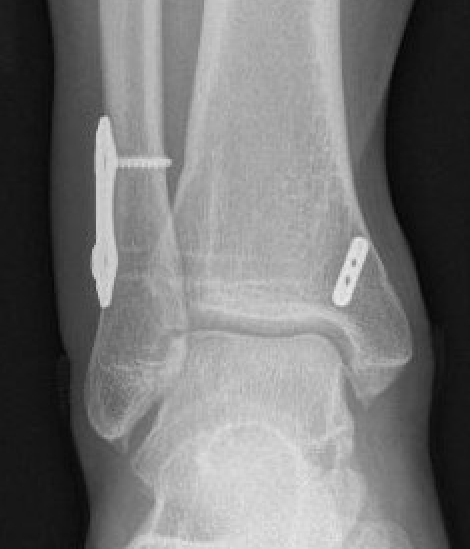

Screw fixation

Technique

Open reduction of the distal tibio-fibular joint

Two screws

- level of syndesmosis (1.5 - 3 cm from joint)

- angle 30 degrees anterior

- 3 or 4 cortices

- 4 cortices probably more likely to break

- insert screws with ankle at neutral dorsiflexion

- consider removal at 4 - 6 months

Suture button fixation

Open reduction of the tibio-fibular joint

Caution in length unstable fractures (consider fixing fibula first)

One or two suture buttons

- 1.5 - 3 cm above joint line